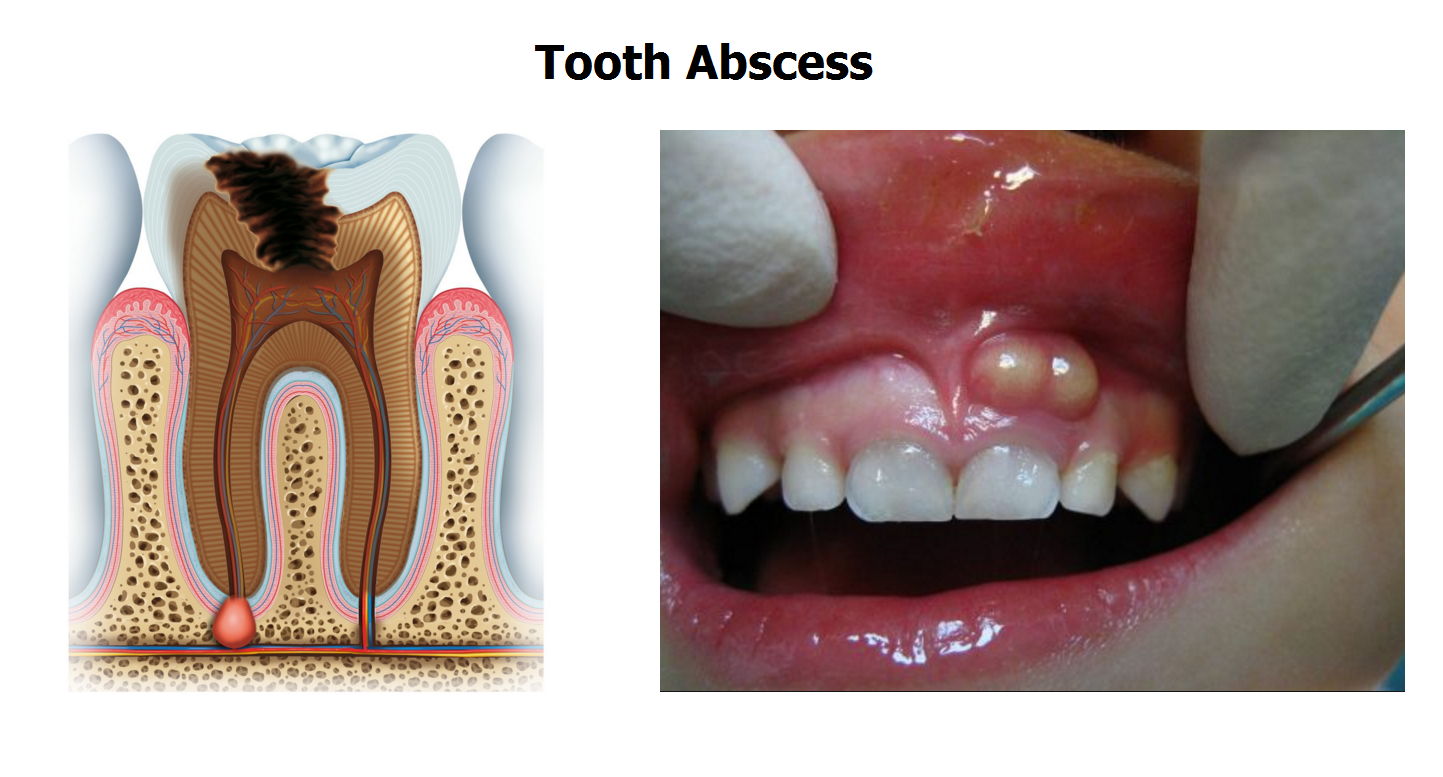

tooth dental decay abscess stages caries dentagama phoenix pain pulp infection teeth bone like spread look mouth periodontal severe enamel

Tooth dental decay abscess stages caries dentagama phoenix pain pulp infection teeth bone like spread look mouth periodontal severe enamel. Symptoms and treatments of dental caries. Stages of dental decay and periodontal disease